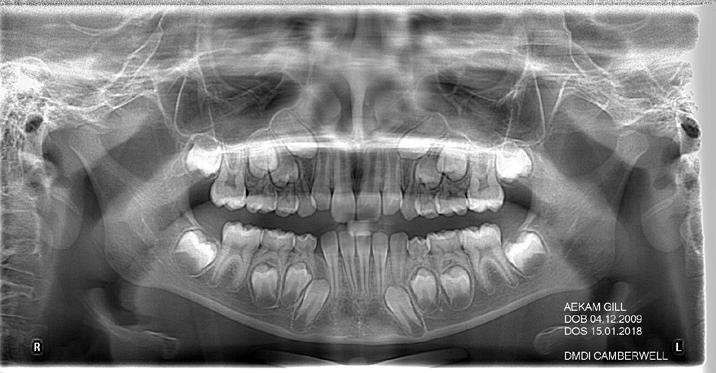

Panoramic radiogram revealed complete permanent dentition with mandibular left impacted wisdom tooth. Roots of the mandibular second bicuspids appeared to be short. There was an excellent bone support and no sign of periodontal or periapical pathology. (Figure 5-B).

Lateral Cephalometric radiogram and tracing revealed robust lower airway (18.0/15mm), CVMS 6, maxilla and mandible are prognathic (SNA - 93° and SNB - 84°), Class II skeletal (ANB –9.0 mm, Witts – 9.0 mm). The patient was hyperdivergent (NS/ GoM – 30°, ALFH - 83 mm!!), protrusive maxillary incisors (U1/ SN – 117.0°), mandibular incisors were within the norm (L1/GoM 95.0°) and Harvold Δ was 30 mm. The soft tissue profile (lips) was convex (Figure 5-C, D).

FIG. 5A: Pre-treatment, TMJ radiogram

FIG. 5B: Pre-treatment, Panoramic radiogram

FIG. 5C: Pre-treatment, Cephalometric radiogram

FIG. 5D: Pre-treatment,Cephalometric tracing